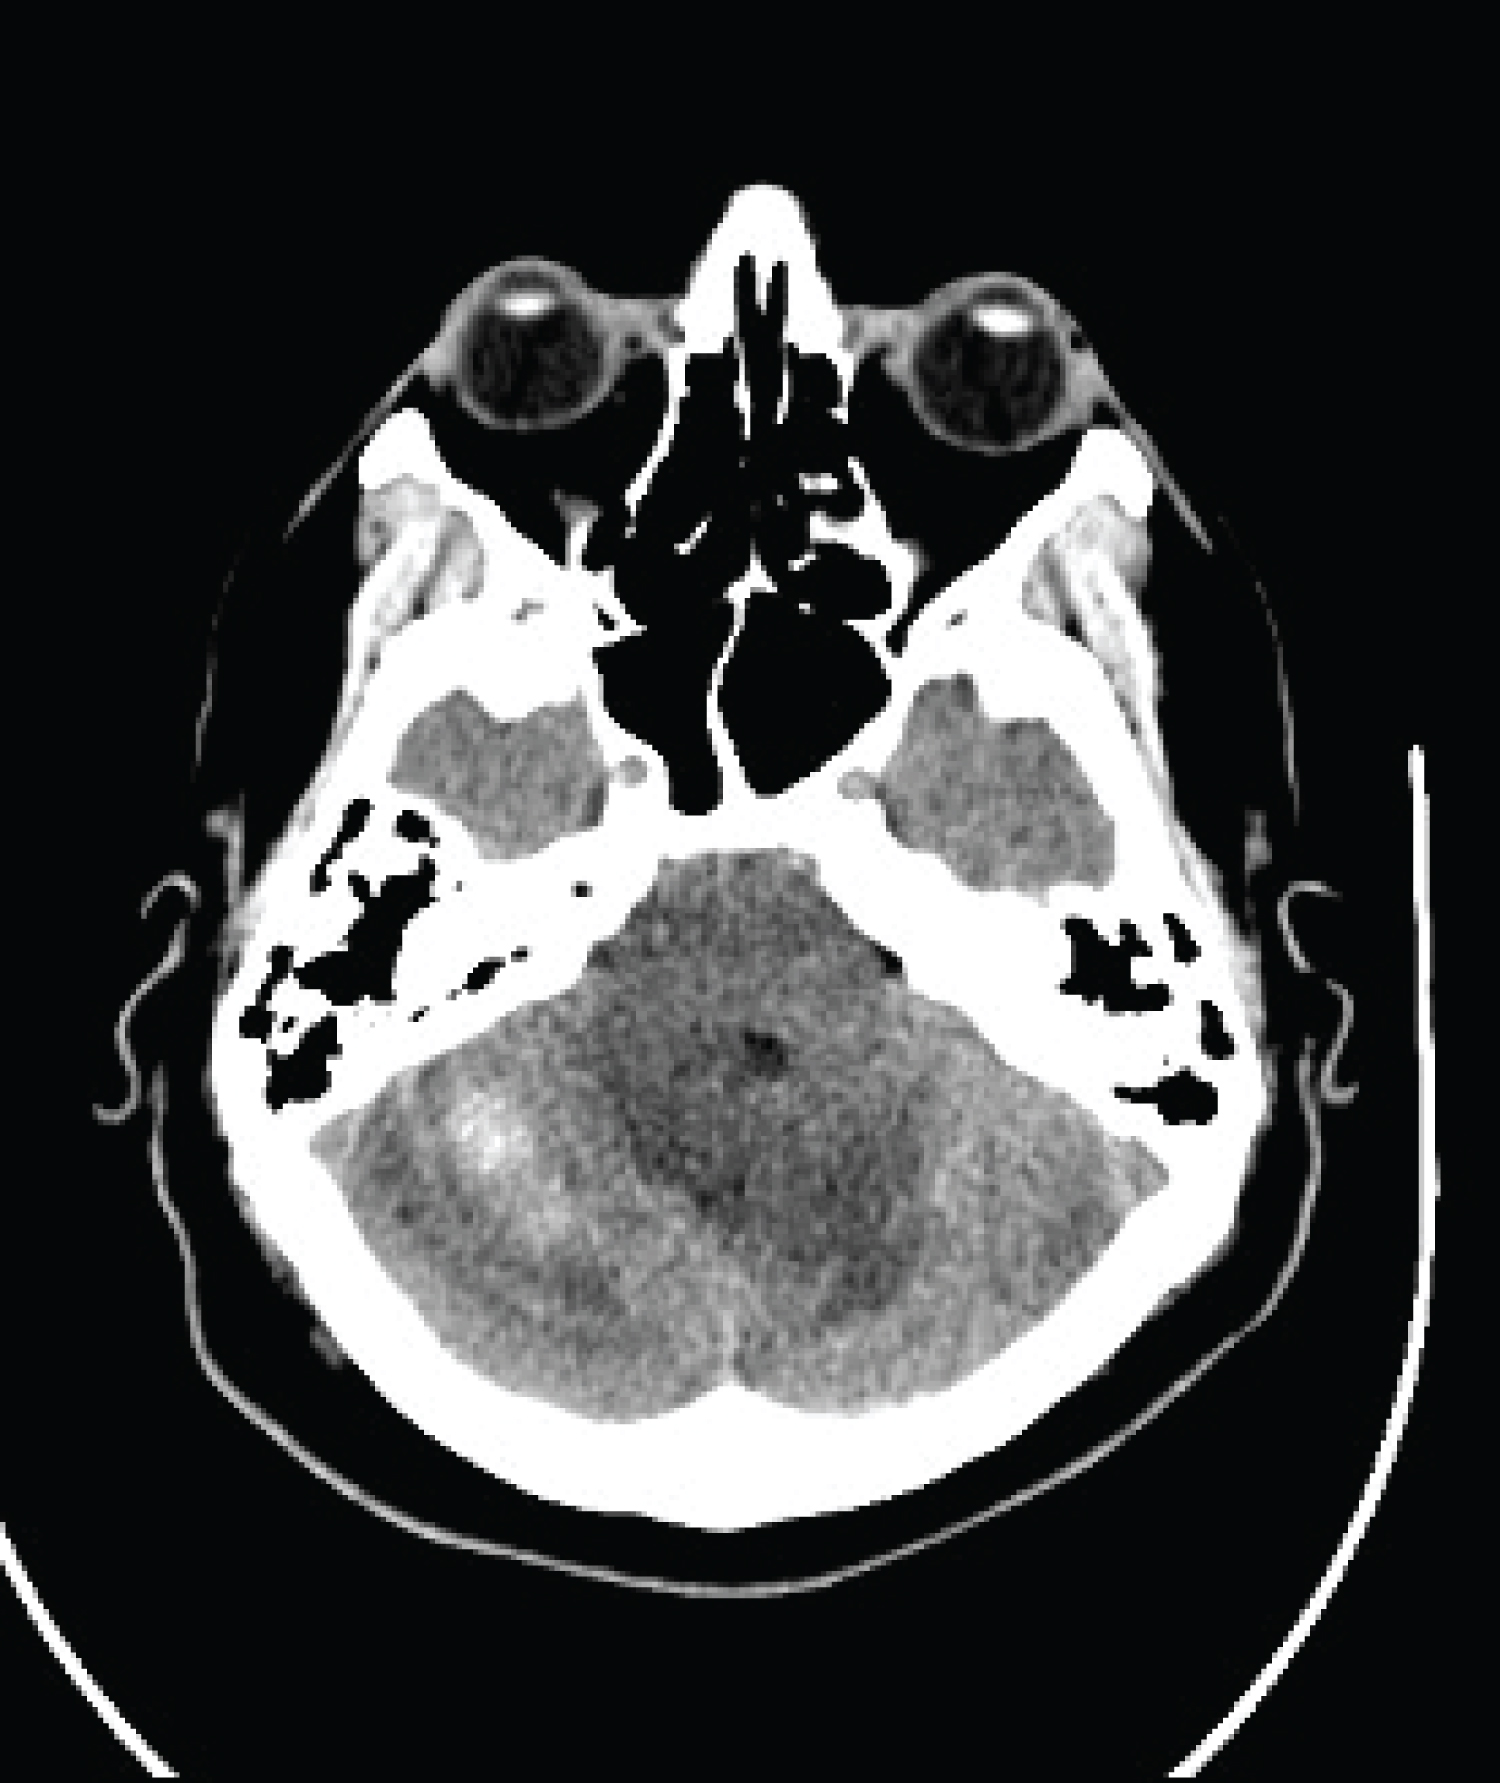

Following the removal of the Hemovac drain, the patient experienced gradual headache relief and improved mental status. Serial head CTs showed no progression and eventual stabilization. Under vigilant care of the neurosurgery and critical care teams, he was discharged on day 18 with a head CT showing diminished hemorrhage, edema, and ventriculomegaly. At follow-up, he demonstrated good mobility with minor balance issues and no headaches, and a repeat CT scan confirmed complete resolution of the cerebellar hemorrhage and significant reduction in edema and ventriculomegaly (Figure 4). He resumed work three months post-surgery.

Figure 4: Head CT without IV contrast 1 month postoperatively demonstrating complete resolution of cerebellar hemorrhage. View Figure 4